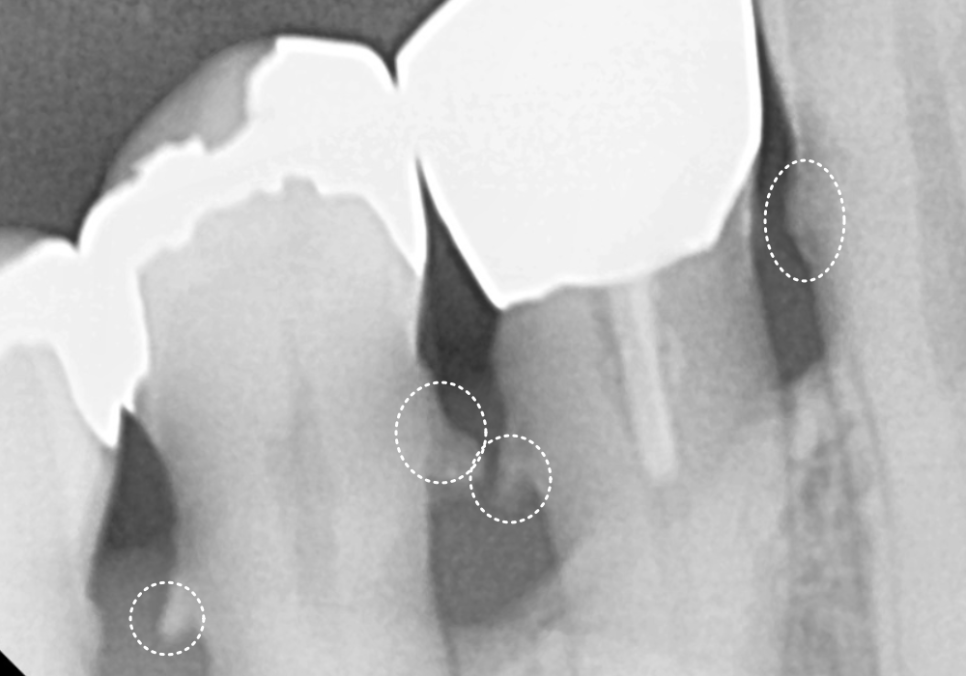

#47 치아: 수직 파절(완전히 쪼개짐)

#47,46,45, #31,32,33, #16,14 : 치아흔들림

전체적인 상태: 잇몸뼈가 녹아

치조골 수평이 매우 낮아진 상태

치료 계획

단순히 치아 하나를 치료해서

될 상황이 아니었기에,

전체적인 재건 계획을 세워드렸습니다.

1 ) 발치 (#16,14, #37,36,35,34, #41~32)

흔들림이 심해 살릴 수 없는 앞니와

어금니들을 발치했습니다.

위쪽 어금니 부위는 뼈가 너무 부족해서

잇몸뼈 위쪽의 빈 공간인

251201

상악동을 들어 올리고 뼈를 채워 넣는

상악동 거상술을 병행하며

임플란트를 식립했어요.